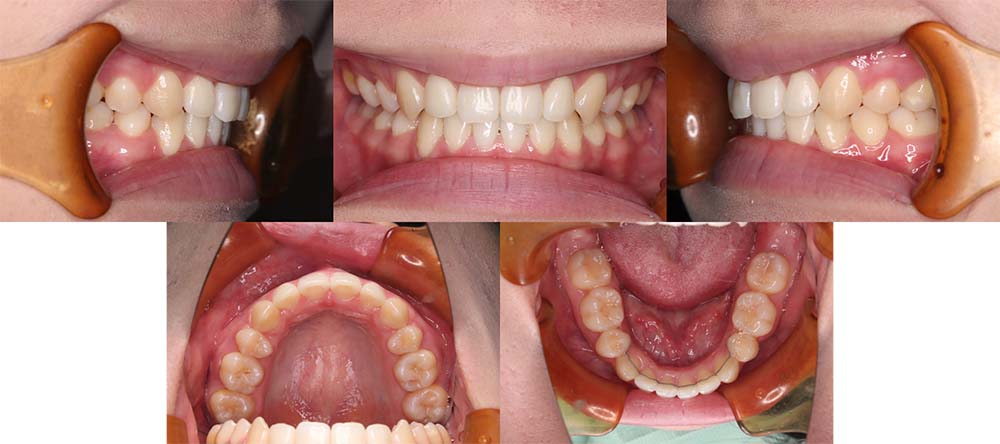

| 症例分類 | 叢生 |

| 診断名 | 上下叢生 |

| 主訴 | 八重歯と下の歯のガタガタが気になる |

| 年齢 | 24歳4ヶ月 |

| 性別 | 女性 |

| 抜歯部位 | 上下左右の第一小臼歯(4本) |

| 使用装置 | 上は裏側、下は表側のワイヤー装置 |

| 治療期間 | 2年8ヶ月 |

| 保定装置 | 固定式保定装置、取り外し式保定装置(8時間) |

| 費用 |

[検査・診断料] ¥49,500 [基本施術料] ¥1,056,000 [調整料] ¥5,500/回 [抜歯] ¥5,500/本 [保定装置] ¥55,000(税込) 抜歯や虫歯治療は他院にて費用が別途かかります。(抜歯¥4,000〜10,000/本)

上下叢生のため、上下第一小臼歯を抜去して上裏側下表側のハーフリンガルで治療しました。

顎間ゴムは治療期間の半年程度使用しましたが、協力度が良好だったためしっかり咬合することができました。

治療開始前にホワイトニングをしたこと、咬合力が強いためか装置の脱離が多く、予定より治療期間が伸びてはしまいました。